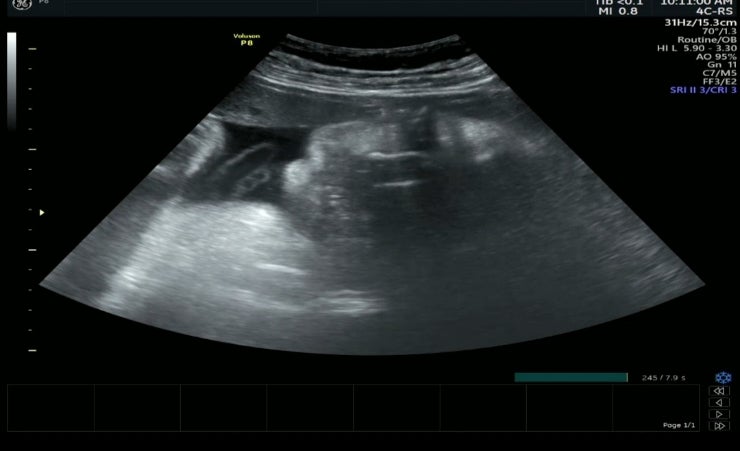

36w 0d 정기검진

안녕 통통아 2주만에 500g늘어서 2994g되신분 거의 3키로네.. 2주에 따박따박 1키로씩쪄서 뭔일이지싶은데 ...